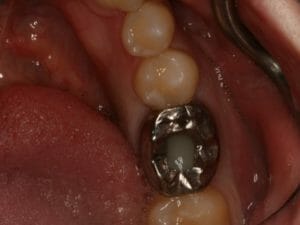

Sinus Graft

One of the most common areas for bone grafting for dental implants in Jacksonville is the upper back jawbone. When our upper molars are removed, there is often only a small amount of bone between the teeth and the sinus cavity. During bone healing, even with a ridge preservation, the sinuses tend to grow into this space, further reducing the available bone for implants. If need be, Dr. Kuznia and Dr. Storch can perform a Sinus Graft, or, enter the sinus cavity through a window about the size of a dime to add a bone graft to this area. If you are considering getting dental implants in Jacksonville, Orange Park, or the surrounding areas, visit one of our four locations today!